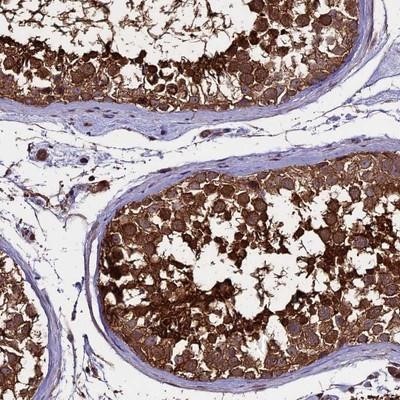

Supportive validation

- Submitted by

- Novus Biologicals (provider)

- Main image

- Experimental details

- Immunohistochemistry-Paraffin: PGPEP1L Antibody [NBP1-90971] - Staining of human testis shows strong cytoplasmic positivity in cells in seminiferus ducts.